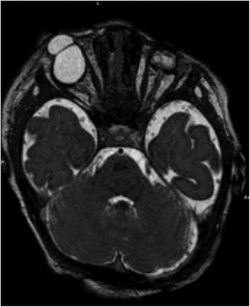

Bilateral cryptophthalmos with microphthalmos in the left ocular globe and abnormal right ocular globe in a female infant with Fraser syndrome. | |